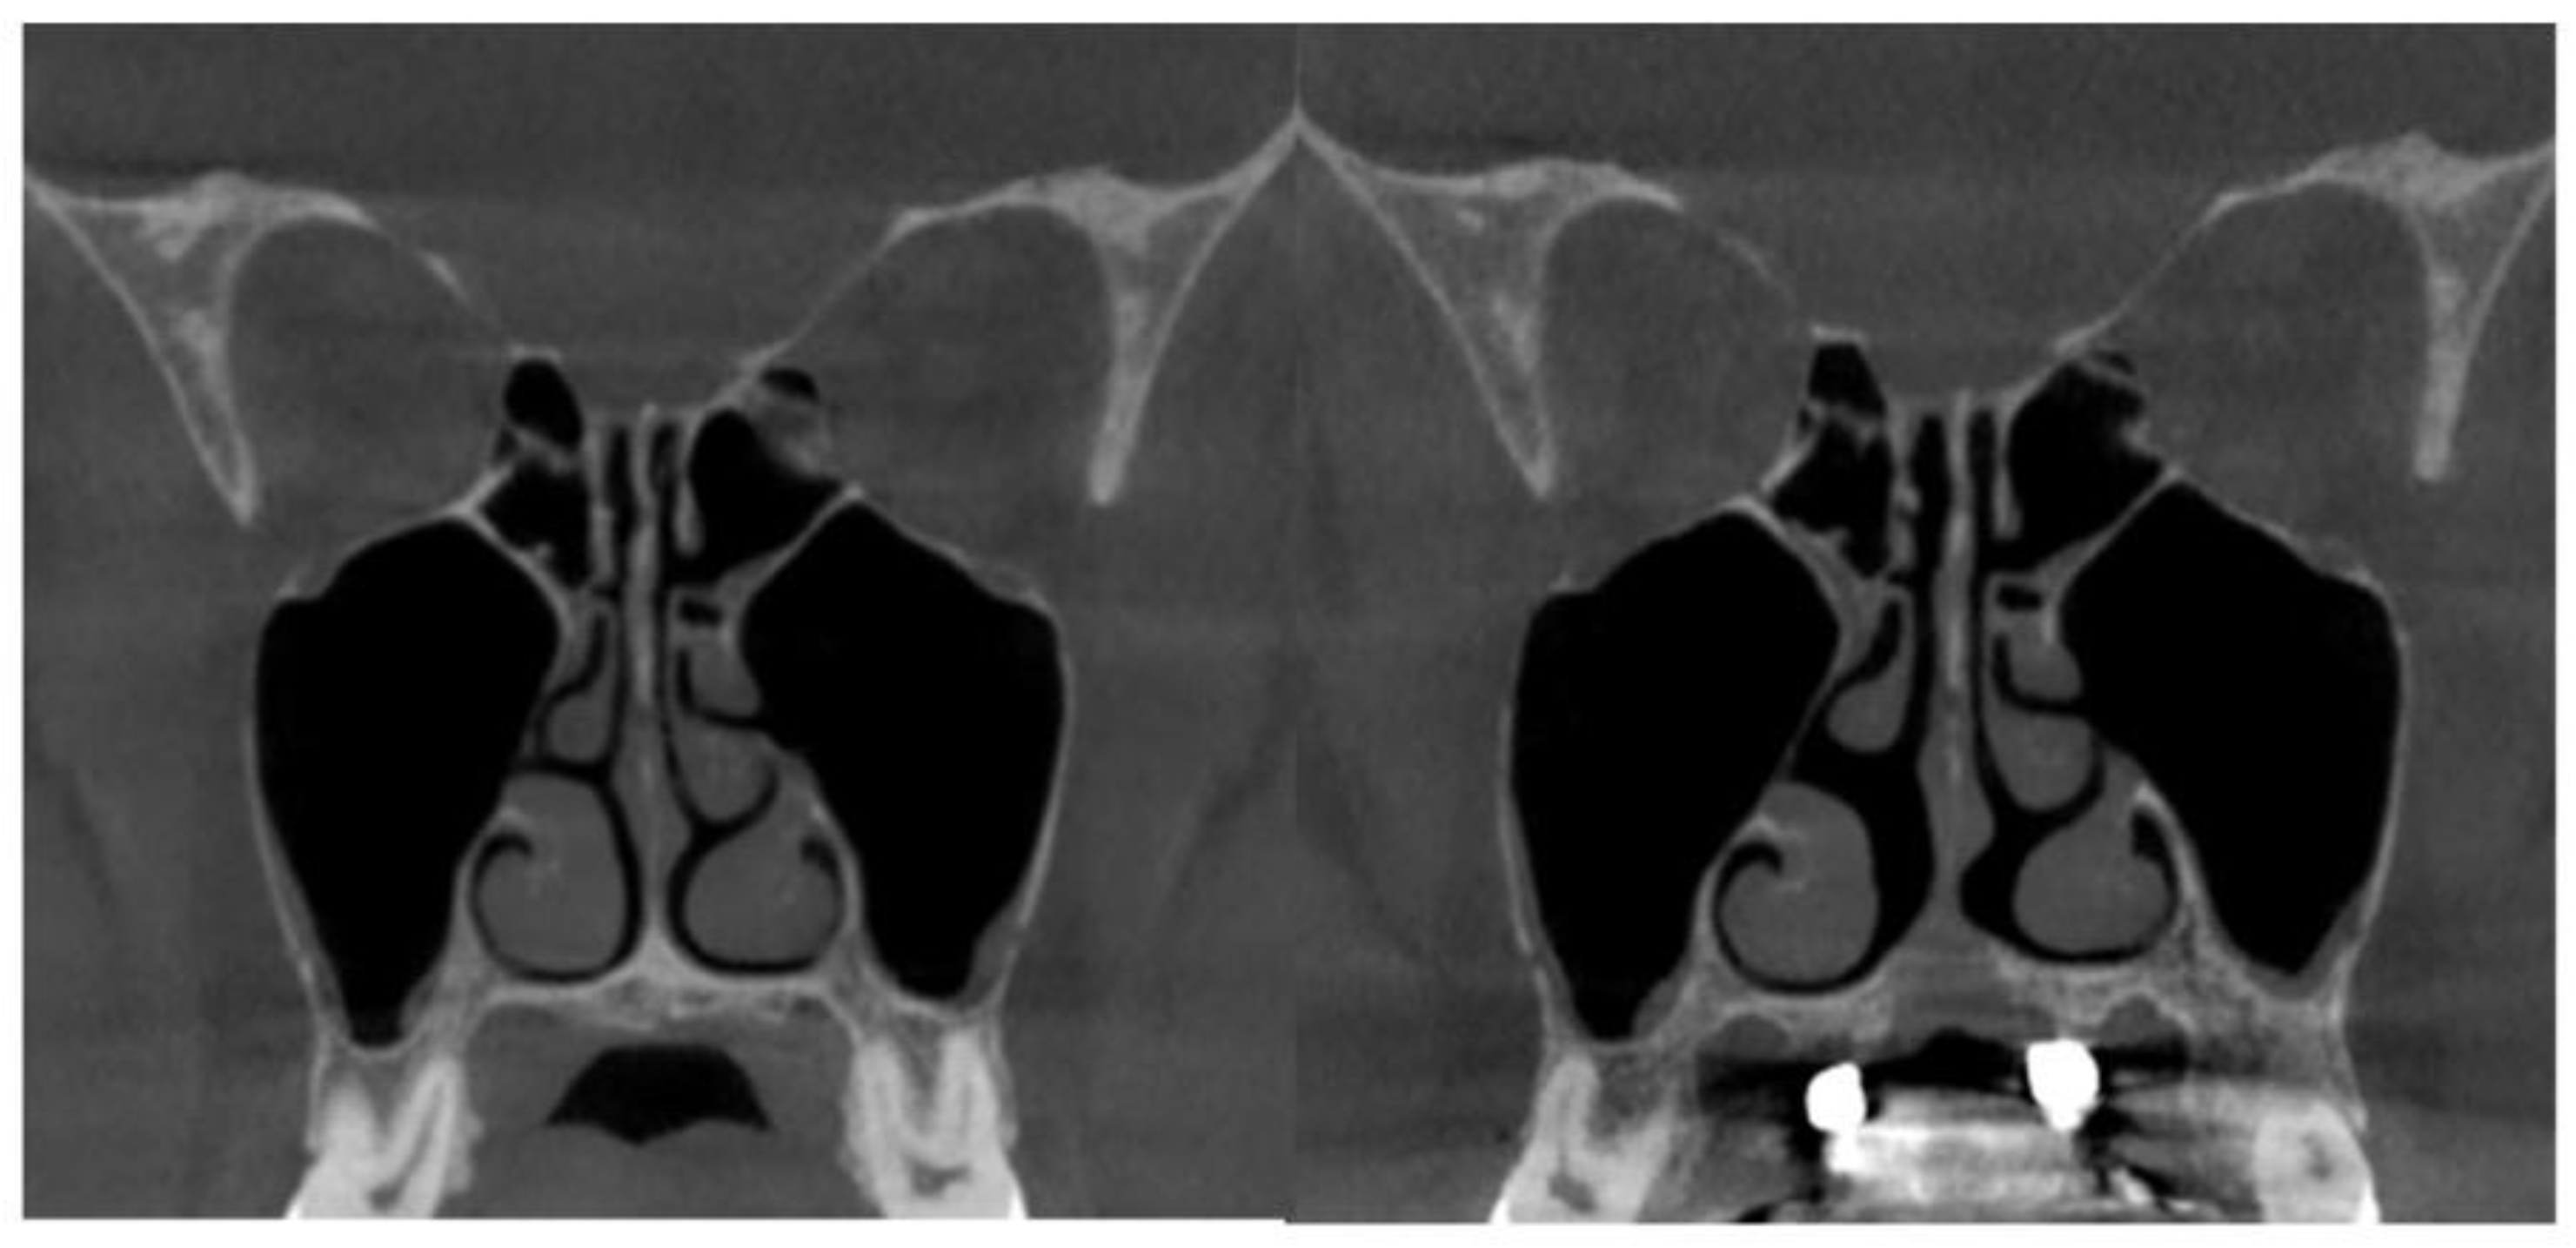

2.7. Case D: Midfacial Asymmetry Correction with Guided Expansion

- Asymmetric expansion with residual attachment of the nasal septum unilaterally to the maxillary crestal bone (Figure 5,6);

- Diagonal fractures of the palatine bone extending from the distal margin of the palatal process of the maxillary bone unilaterally, often associated with pain and tension;

- Asymmetric displacement of the nasal base floor with unilateral downward and outward movement (Figure 5,6)

- Downward inclination and displacement of the alveolar process on the ipsilateral side (Figure 5,6);

- Unilateral soft tissue shift, including nasal ala and corner of the mouth displacement toward the side of unattached separation.